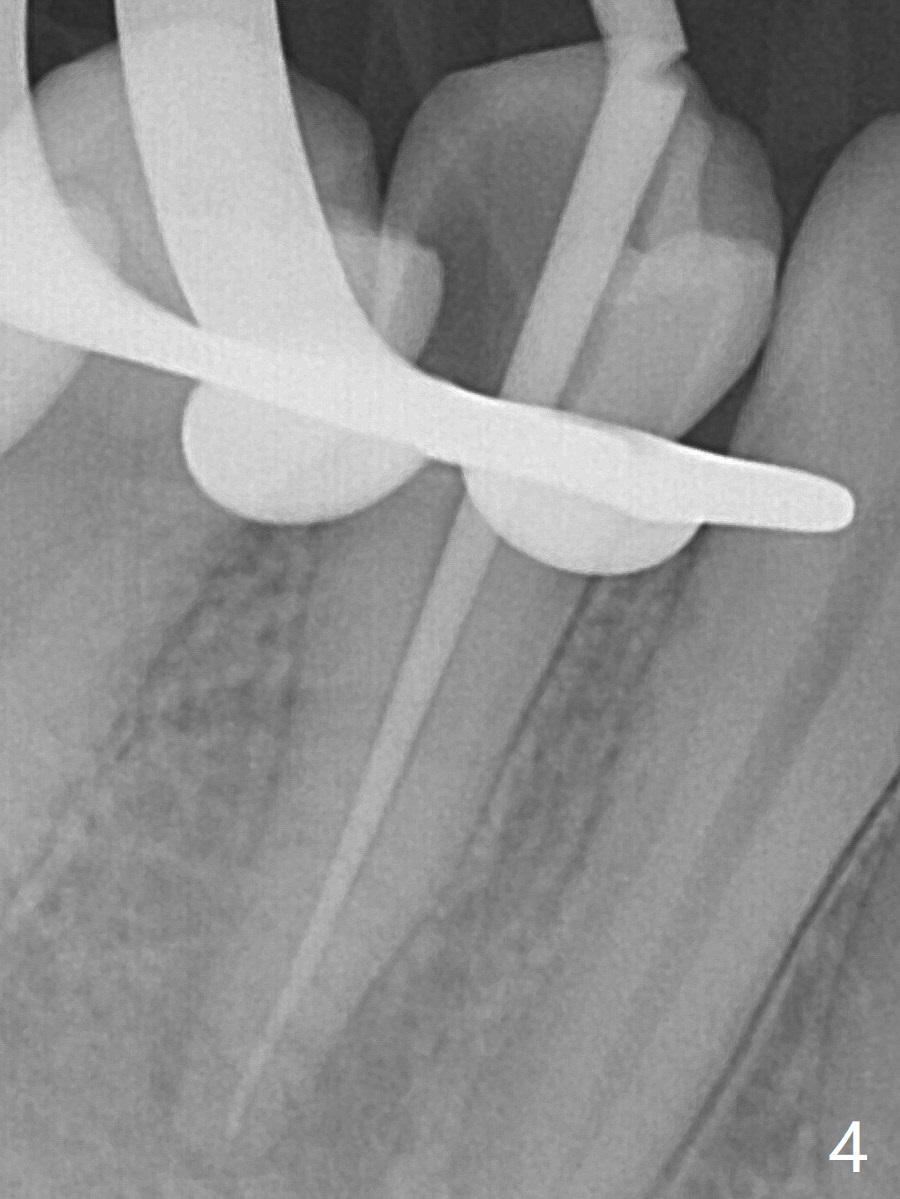

25岁硕士生,女,要求右下4补牙(图一:第一前磨牙),经过解释,欣然接受根管治疗。后者要领基本四条:无菌,根管笔直通畅,使用根尖定位仪和旋转式锥形扩大针和锥形牙胶尖。为了无菌,局麻后常规使用橡皮障(图二 *)。防止断针,尤其是旋转式锥形扩大针,根管治疗开口尽量大(图二箭头),保持扩大针笔直。开始根尖定位仪有点毛病,使用15号锉测定根管长度,不小心超越根尖大约3毫米(图三)。后来倒退4毫米,并得到根尖定位仪证实,主牙胶尖(30/.06)好像长度合适(图四),反复冲洗,最后再插入一个细牙胶尖一次性完成根管治疗和补牙(图五,六)。